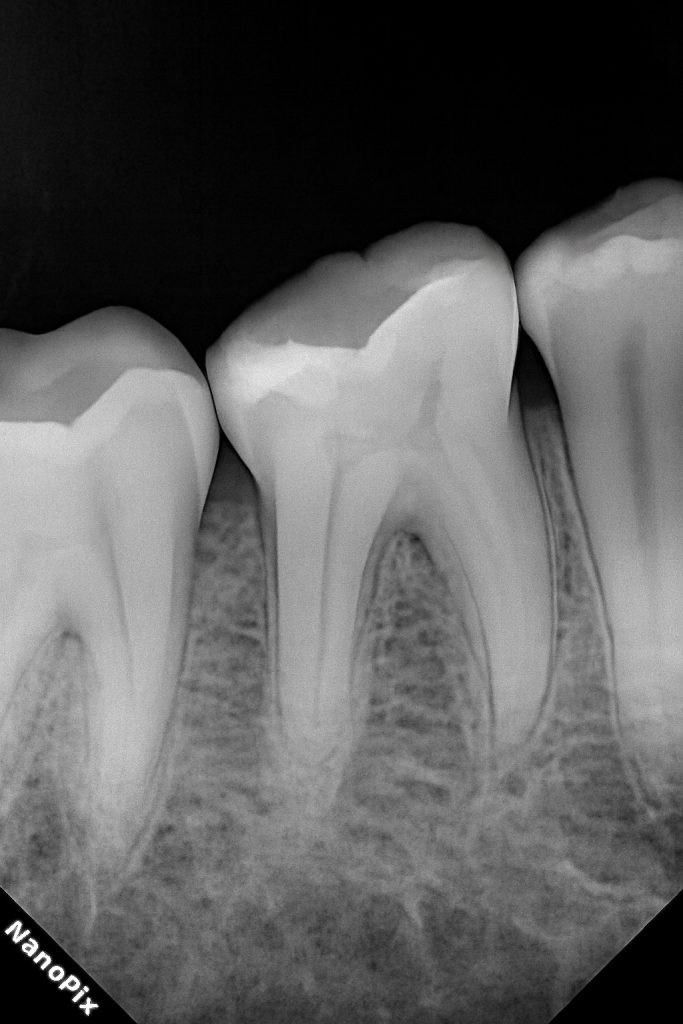

Radiographs (Pre-op)

Image 1–2:

“Pre-operative bitewing radiographs showing proximal caries in posterior trio, with preserved pulp vitality and no signs of apical pathology.”